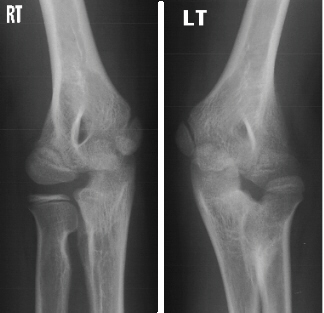

The patient is an 11 year old, otherwise completely healthy

boy, who presented for evaluation of his left arm. He states he

has always had limited range of motion of his left arm, however,

his mother states that it was not until recently she became concerned.

The patient is right hand dominant. This does not cause him any

functional problems and he has no pain. The mother and boy are

concerned because the right and left arms are different. The left

arm demonstrates a shoulder with full range of motion (ROM) and

strength 5/5. The elbow has a flexion from 0 to 135 degrees, but

the forearm is fixed in 45 degrees of pronation without active

or passive supination. The wrist has full ROM with some hyper-mobility,

especially in radial and ulnar deviation. The strength is 5/5

in elbow flexion/extension, wrist flexion/extension and grip.

He is neurovascularly, intact. The right arm also demonstrates

normal motion at the elbow with flexion from 0-135 degrees but

limited supination from 0-50 degrees and pronation from 0-20 degrees.

The remainder of his exam was normal.